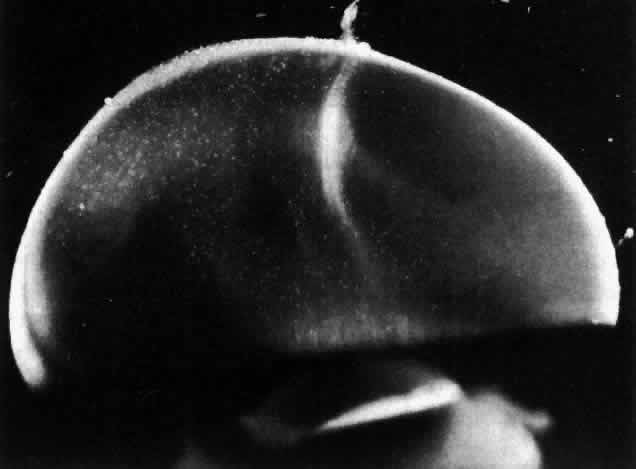

The posterior vitreous cortex is 100-110 μm thick50,60 and, as shown in Figure 12, consists of densely packed collagen fibrils.50,60,152 There is no vitreous cortex over the optic disc (see Figs. 4A AND 13), AND the cortex is thin over the macula due to rarefaction of the collagen fibrils.50 The prepapillary hole in the vitreous cortex can sometimes be visualized clinically when the posterior vitreous is detached from the retina (Fig. 14). If peripapillary glial tissue is torn away during PVD and remains attached to the vitreous cortex about the prepapillary hole it is referred to as Vogt's or Weiss's ring. Vitreous can extrude through the prepapillary hole in the vitreous cortex (see Fig. 4A) but does so to a much lesser extent than through the premacular vitreous cortex (see Figs. 4B AND D and 13). Jaffe153 has described how vitreous can extrude into the retrocortical space created after PVD and has proposed that persistent attachment to the macula (Fig. 15) can produce traction and certain forms of maculopathy.154,155 Although there are no direct connections between the posterior vitreous and the retina, the posterior vitreous cortex is adherent to the internal limiting lamina of the retina, which is actually the basal lamina of retinal Müller cells. The exact nature of the adhesion between the posterior vitreous cortex and the internal limiting lamina is not known but probably results from the presence of various extracellular matrix molecules.91 This concept is supported by studies156,157 in which vitreous cortex separation from the retina was induced using agents that acted on extracellular matrix components that could bind the posterior vitreous cortex to the internal limiting lamina of the retina.

Fig. 14. The posterior vitreous is detached, and the prepapillary hole in the posterior vitreous cortex (arrows) can be seen anterior to the optic disc (slightly below and to the left of the optic disc) (Sebag J: The Vitreous--Structure, Function and Pathobiology. New York, Springer-Verlag, 1989)